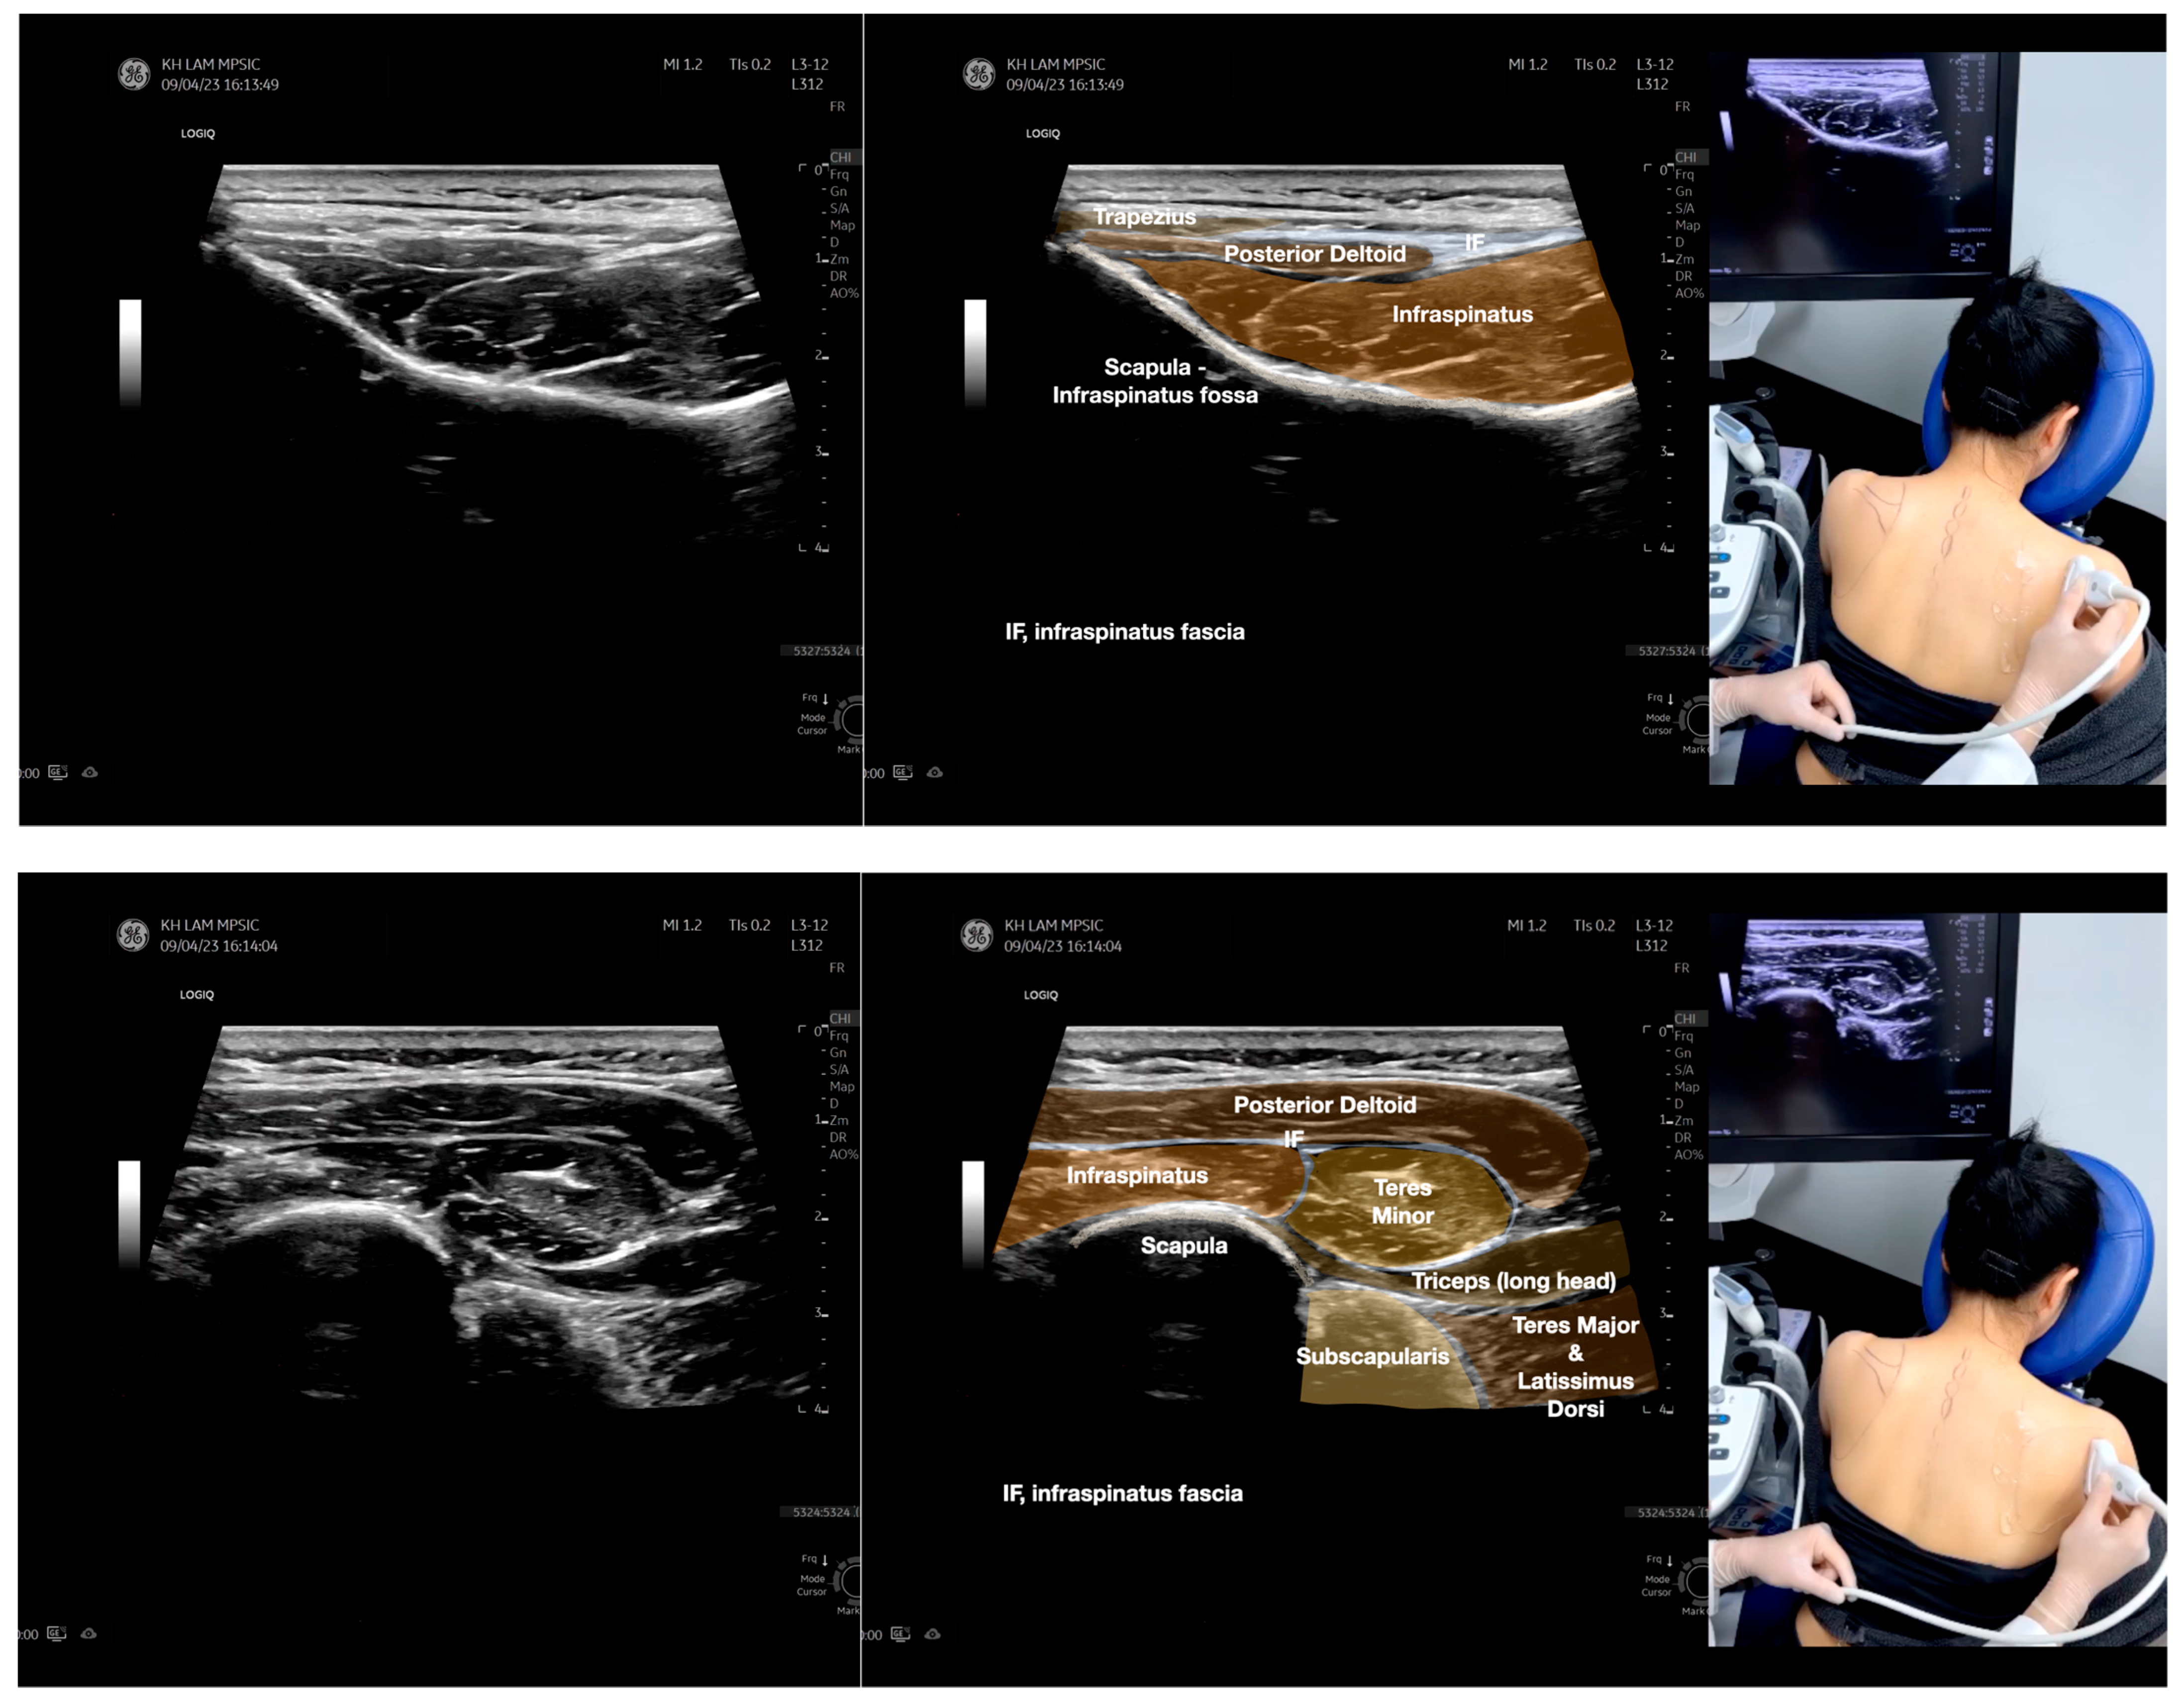

Figure 5.

Sonoanatomy of scanning the infraspinatus fascia in the sagittal plane from the rhomboid minor laterally, then back to the rhomboid major. The step-by-step scanning techniques of the structures illustrated in this figure have been shown in Video S9. Available online: https://www.dropbox.com/s/gu9hhrdq9erin6n/Figure%205.docx?dl=0 (accessed on 1 January 2023).